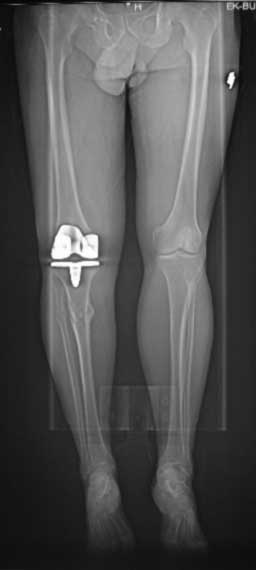

У пациента 50 лет имеется разгибательная контрактура через 8 меспосле ТКА. Уважаемые коллеги. Пациент 8 мес после операции ТКА, в анамнезе – неправильно сросшийся перелом голени, коррекция оси (снимки прилагаются. В настоящее время имеется разгибательная контрактура 10/5/0, на операционном столе было 90/0/5, на момент выписки движения 50/0/0 в надежде на дальнейшую разработку. До эндопротезирования 40/10/0. Глубокая инфекция исключена. Ротация бедренного компонента в норме (по КТ). Вопросы: насколько для такого ограничения критична некорректная установка б/б компонента (я намерял 7 град)? Причина нынешнего состояния, артрофиброз? Какие действия следует предпринять, удаление рубцов, релиз головок 4-главой мышцы? Что-либо другое, ваше мнение? С уважением, Максим Агалаков, Екатеринбург.

Низковат, соласен. Соориентируетесь при операции, если ограничивает движения, перенести бугристость или Z-образная тенотомия связки надколенника, артросокпический артролиз обязательно.